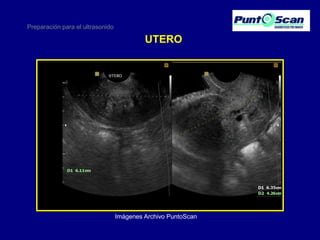

UTERO

Imágenes Archivo PuntoScan

Preparación para elultrasonido UTERO Imágenes Archivo PuntoScan

• 20.